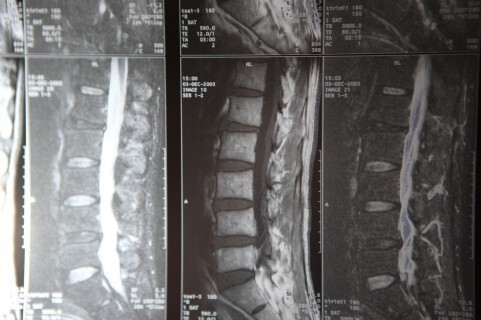

mriherunia

上の写真はMRIの画像です。

腰椎椎間板ヘルニアの方の画像です。